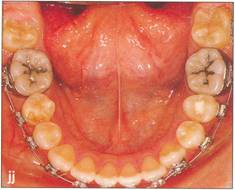

Fi 545e45f g S.8a Preoperative panoramic view. The maxillary left first premolar will be extracted for orthodontic reasons and transplanted to the area of mandibular left second premolar in a 15year-old female. Fi 545e45f gs S-8b to 5-89 Preoperative intraoral view. Fi 545e45f g S-8h Preoperative view. |

Fi 545e45f g 5-8jj Completion of orthodontic movement. |

Fi 545e45f gs 5-8kk to Fi 545e45f g 5-8nn Two years 6 months after transplantation. |